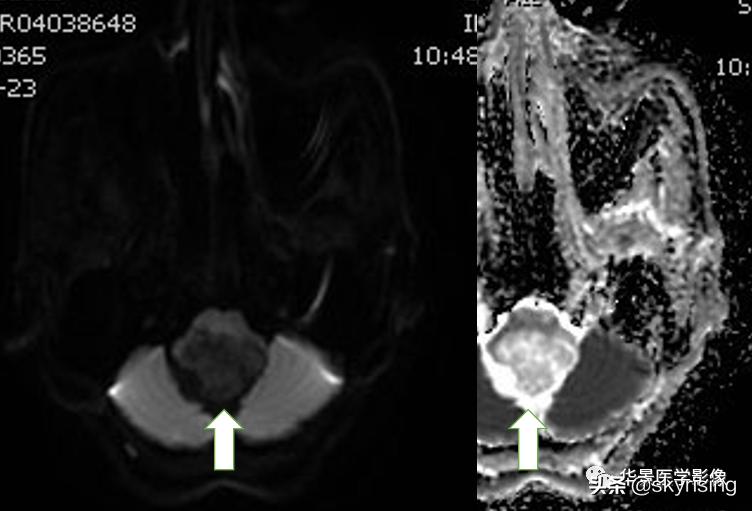

以下依次为T2WI、FLAIR、T1WI、增强、DWI及ADC:

上图白色箭头:病灶呈DWI低信号,ADC高信号,信号欠均,提示弥散不受限。

小脑延髓池内见不规则异常信号影,呈长T1长T2信号,内部信号不均,边缘见稍粗大流空信号血管影,FLAIR少许片状低信号,增强呈明显强化,DWI不均质低信号,ADC不均质高信号。小脑半球、延髓、第四脑室受压变形。临近延髓变窄,呈长T1长T2信号。

形态特点:肿瘤多类圆形,60%囊实混合性,大囊小结节,增强囊性部分无强化,囊壁若为肿瘤细胞可有环形强化,40%实性,周围可有水肿,增强明显强化,肿瘤周围及内可见血管流空信号影为典型特征。DWI为低信号。